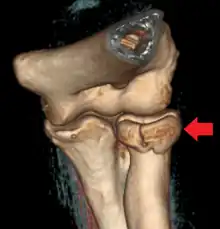

CT scan demonstrating the Mason type III radial head fracture -

Radial head fracture seen on 3D CT reconstruction